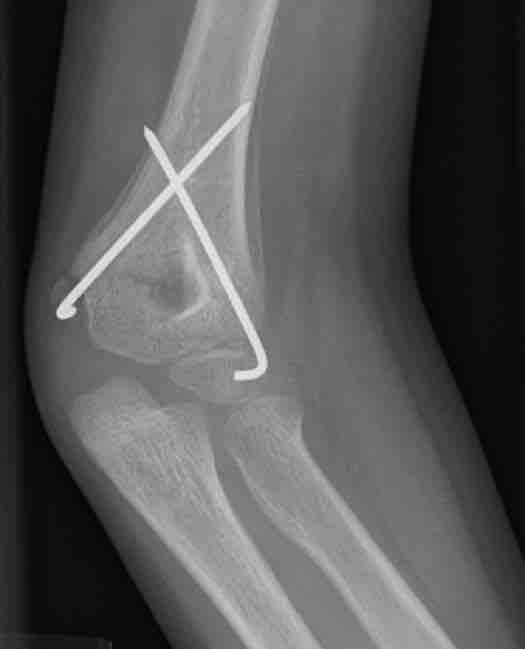

Bone repair

This figure depicts a communitive midshaft humeral fracture with callus formation.

This is an x-ray image of a broken arm. It shows a communitive midshaft humeral fracture with callus formation.